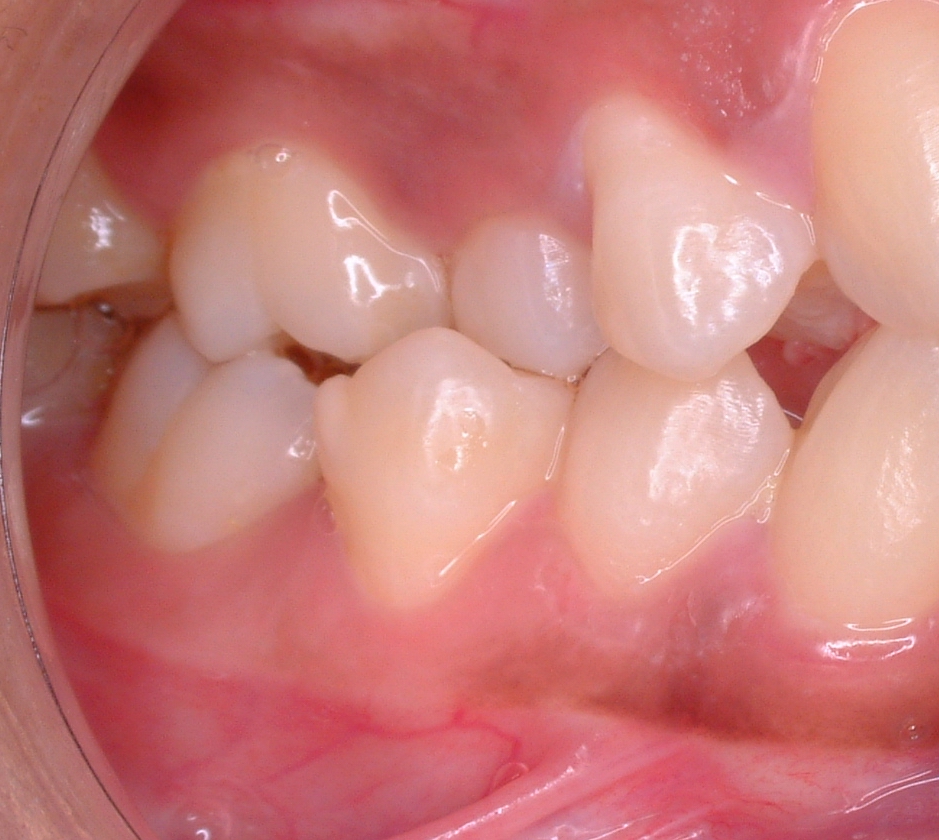

4. 3. 덧니 (Crowding)

치아 덧니는 치아가 올바르게 정렬되는 데 필요한 공간이 부족하여 발생한다. 이는 턱뼈 크기에 비해 치아가 너무 크거나, 치아가 나올 공간이 부족할 때 나타난다. 덧니의 정도는 다음과 같이 분류한다.[25]- 0-4mm = 경미한 덧니

- 4-8mm = 중간 정도의 덧니

- 8mm 초과 = 심한 덧니

덧니는 대개 치아 발치, 투명 교정 장치, 또는 치아 교정기를 사용하여 교정 치료를 받으며, 소아의 경우 성장 조절, 성인의 경우 악교정 수술이 뒤따르기도 한다. 드물게 턱을 늘리거나 줄이기 위한 수술적 재형성(악교정 수술)이 필요할 수 있다. 철사, 판 또는 나사를 사용하여 턱뼈를 고정할 수 있으며, 이는 턱 골절의 수술적 안정화와 유사하다. 대부분의 사람들은 치아 배열이 "완벽"하지 않지만, 대부분의 문제는 매우 경미하여 치료가 필요하지 않다.[39]